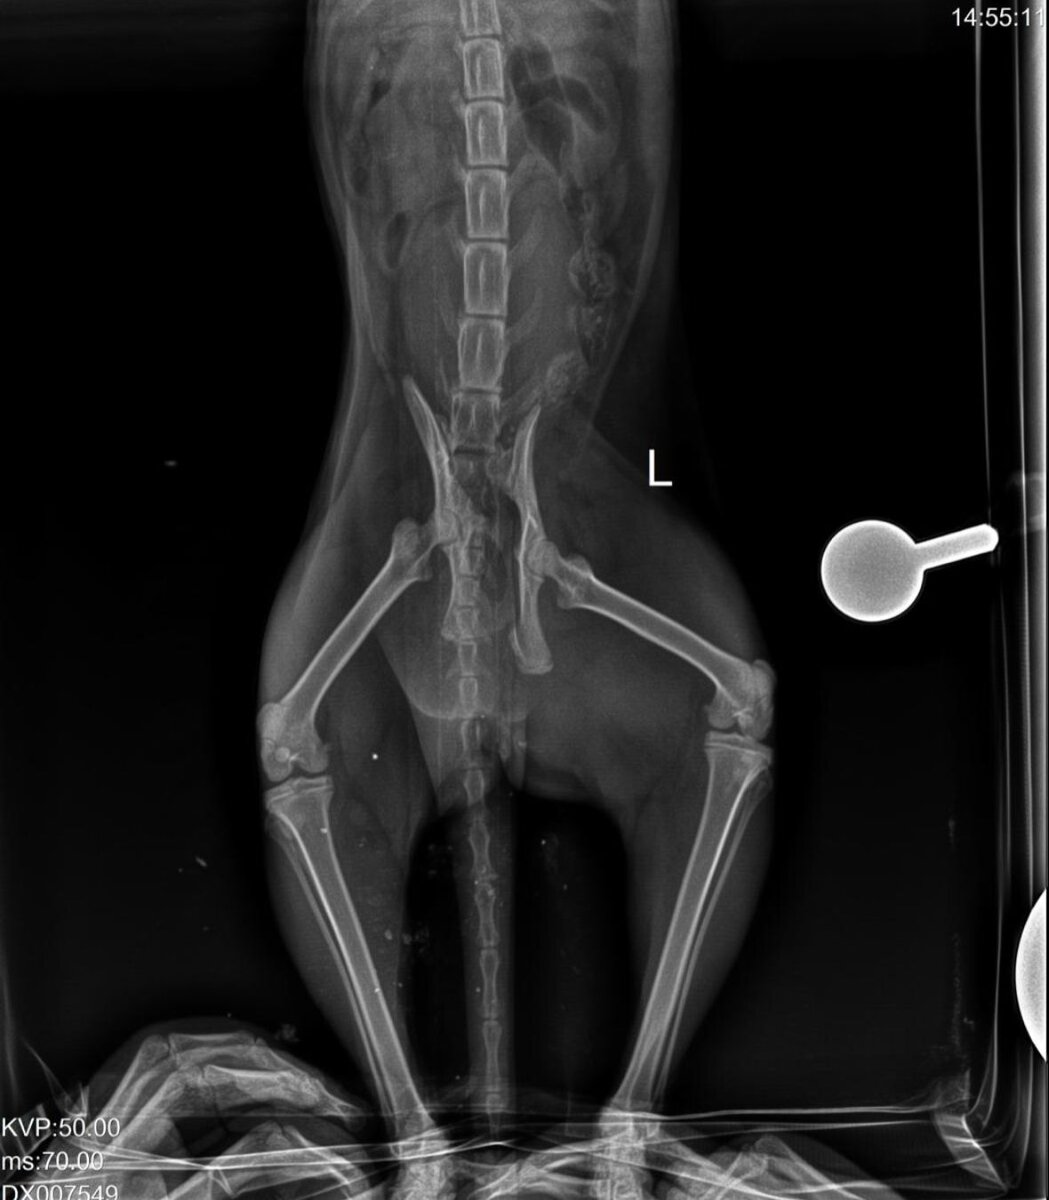

Кошка вялая, буквально тряпочка. Назвали Хондой. Ее сразу отправили на УЗИ, рентген. Выяснилось, что у нее перелом таза со смещением, перелом позвоночника у основания хвоста и что кошку мучала дичайшая боль... Но даже с ней она ни когтем, ни зубом не тронула ветработников, позволяя с собой делать все. А ведь ей всего 8 месяцев... Чувствительность в лапах сохранена, хоть и с сильным торможением, и это вселяет надежду на то, что она будет ходить... Но об этом можно будет думать позже. Гораздо позже. Под вопросом и операция - а это увеличивает стоимость лечения в разы...

Пока Хонде нужна реабилитация. А это значит – ежедневный курс лекарств и обработок, еженедельно рентген в двух проекциях, каждые две недели УЗИ и контроль врача. И кроме того, нужен стационар, нужна сдача анализов... Привезшая все это не потянет сама, цены просто космические. Уже потрачена огромная сумма, а впереди куда как больше...